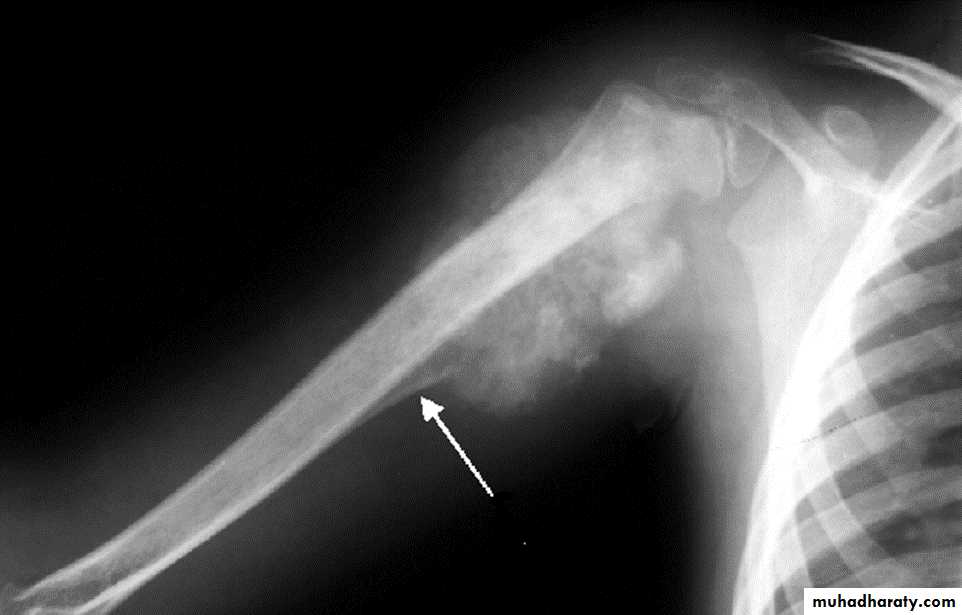

Characteristic of ewings sarcomaTumor have slender pedicle directed from growth plate ,,, what it could be ???

Answer:Osteochondroma Most common benign bone lesion which have their own growth plate).

Pedunculated: slender pedicle directed away from growth plate .

The thickness of the cartilage cap above the bony projection is very important

if the thickness > 1 cm of cartilaginous cap by CT, > 2 cm by MRI give high possibility of Malignant transformation

Also Dispersed calcifications in the cap